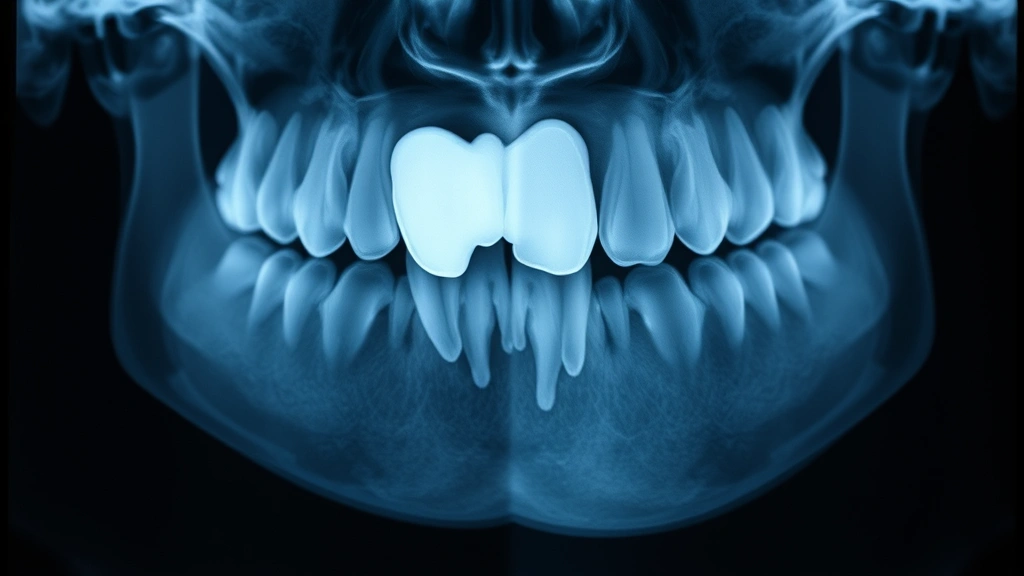

Tooth Root Complexity influences surgical difficulty. Curved, long, or multiple roots make extraction trickier and pricier. Your dentist can see root configuration on X-rays before quoting you, so ask for specifics during your consultation.